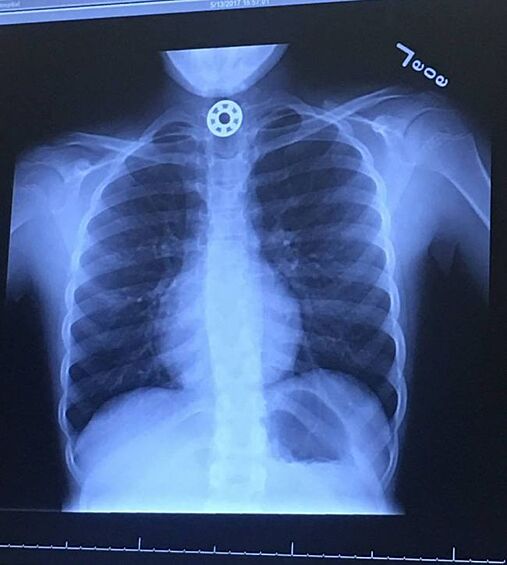

12 рентген‑фотографий, которые доказывают: идиотизм неистребим

Зачем и почему люди глотают разные странные вещи? Никто не знает точно, но медики утверждают, что таких “умников” гораздо больше, чем мы думаем.

Рентгенологи — люди с особо развитым чувством юмора. То, что они порой видят на снимках, у нормального человека вызовет настоящую истерику — а они только хмыкнут и отправят к хирургу. Что поделать, не расстраиваться же из-за каждого курьеза.